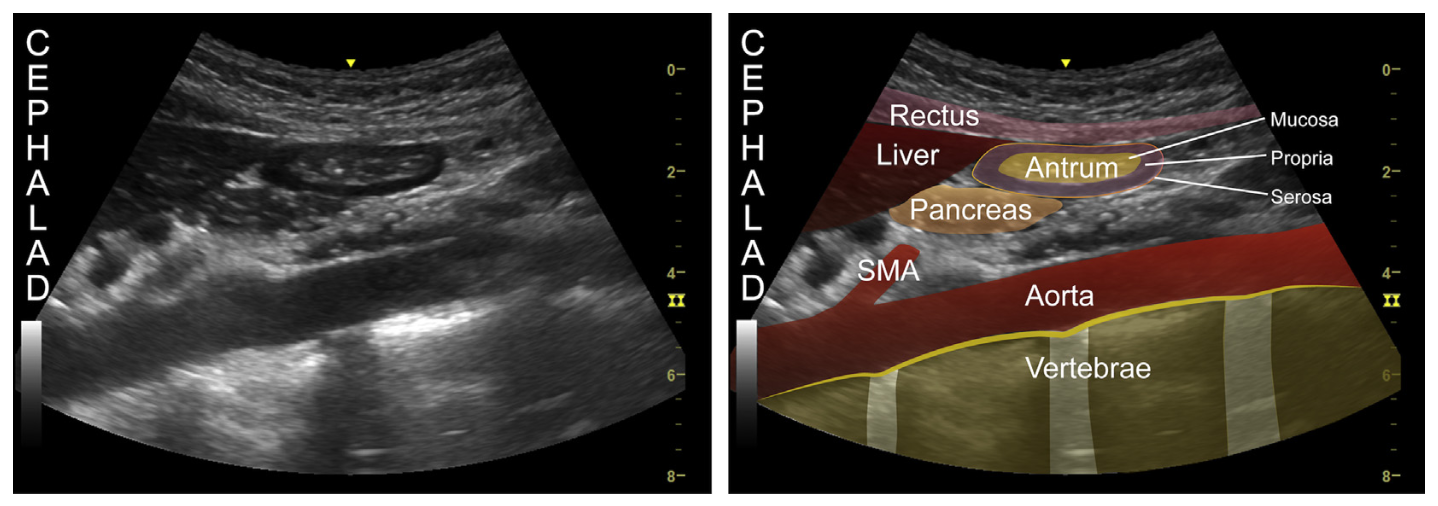

- The focused questions:

- Is the stomach empty or full ?

- If clear fluid is present in the stomach – calculating the volumen in the stomach

- Does the content in the stomach represent a risk for the patient ?